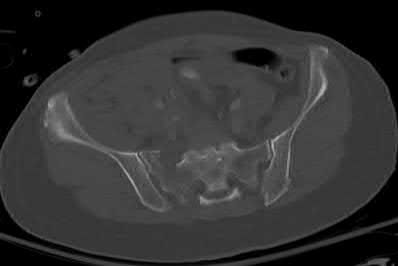

A 35 year-old female presents after prolonged extrication from a motor vehicle collision complaining of severe pelvic pain. Physical examination reveals diminished perianal sensation. She is otherwise neurologically intact. Figures A through D are radiographs and representative CT cuts of her injury. Which of the following nerve roots has likely been injured by the acute trauma?

The clinical scenario is consistent with a high-energy sacral fracture. The radiographs in figures A and B demonstrate a sacral fracture with posterior displacement of the right hemipelvis seen on the inlet view. Figures C and D are axial and sagittal CT images which show a displaced fracture of the right

hemisacrum along with a transvere fracture component through the S3 body . Diminished perianal sensation is concerning for an S2 nerve root injury.